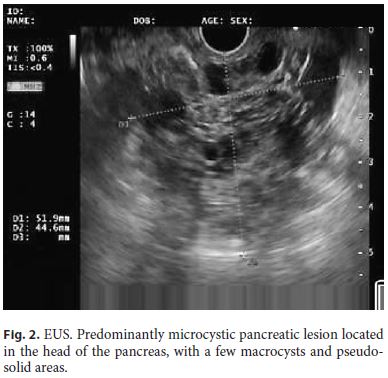

Endoscopic ultrasound (EUS) documented a predominantly microcystic lesion located in the head of the pancreas, measuring 53 × 46 mm, with a few macrocysts and pseudo-solid areas, compressing the CBD and the superior mesenteric vein, and without vascular invasion or Wirsung dilatation (Fig. 2). Fine-needle aspiration of the macrocyst and of a pseudo-solid area was performed. Cyst fluid biochemistry analysis revealed a high amylase level (54,085 UI/L) and a low CEA (2 ng/mL). EUS-fine-needle aspiration cytology showed cuboidal cells, negative for CK8/18, synaptophysin, and chromogranin-A (Fig. 3). For jaundice palliation, endoscopic retrograde cholangiopancreatography (ERCP) was then performed, and a plastic stent was placed. During ERCP, incidental pancreatic duct cannulation and contrast injection occurred, and pancreatography showed a multicystic lesion in the head of the pancreas and confirmed MPD communication (Fig. 4).